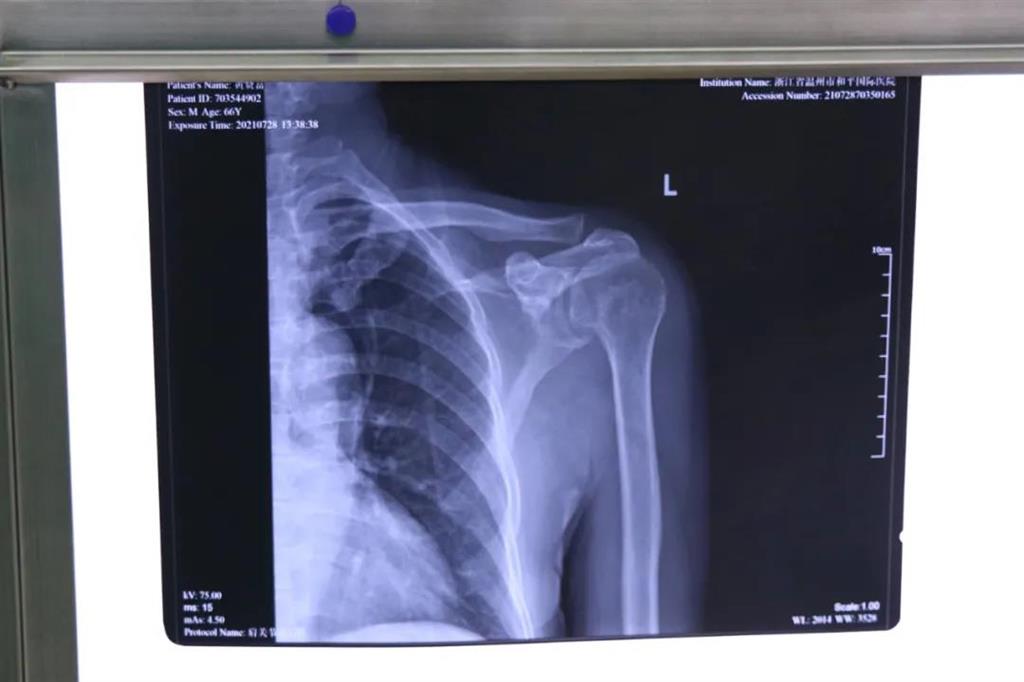

患者黃大叔(66歲)為"左肩袖損傷"病人,8年來(lái)左肩部持續(xù)疼痛伴肩關(guān)節(jié)活動(dòng)輕微受限?;颊哂诮谧蠹绮刻弁醇又?,抬肩困難,難以完成穿衣服等日常生活活動(dòng)。

術(shù)前檢查見(jiàn)左肩關(guān)節(jié)輕度腫脹,左肩關(guān)節(jié)岡上肌附著處壓痛明顯,MRI提示左岡上肌肌腱斷裂回縮,岡下肌腱部分撕裂。為此和平國(guó)際醫(yī)院關(guān)節(jié)鏡微創(chuàng)團(tuán)隊(duì)為患者制定了詳細(xì)的一期、二期手術(shù)方案。此次手術(shù)為一期肩袖成形術(shù)

常規(guī)手術(shù)方式是傳統(tǒng)切開(kāi)肩袖縫合術(shù),但缺點(diǎn)就是創(chuàng)傷較大,切口較大,術(shù)后康復(fù)困難,視野較小,難以處理其他合并傷。目前更先進(jìn)的技術(shù)是采取肩關(guān)節(jié)鏡微創(chuàng)手術(shù),術(shù)中探查肩袖撕裂口,并將其縫合固定

在和平國(guó)際醫(yī)院關(guān)節(jié)鏡微創(chuàng)團(tuán)隊(duì)的協(xié)作下,手術(shù)順利,成功用微創(chuàng)肩關(guān)節(jié)鏡進(jìn)行肩袖修補(bǔ)術(shù)。術(shù)中、術(shù)后患者幾無(wú)出血,且手術(shù)切口小,美觀,患者左肩部疼痛得到明顯緩解。